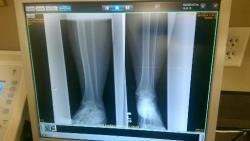

Clearwater,FL-XRay Becky

Tuesday, June 23, 2015 4:52:23 PM, From: jim, To: Stories